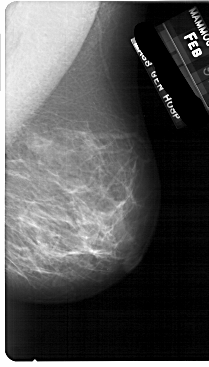

A_1710_1.RIGHT_MLO

LEFT_MLO LINES 5491 PIXELS_PER_LINE 3376 BITS_PER_PIXEL 12 RESOLUTION 43.5 OVERLAY